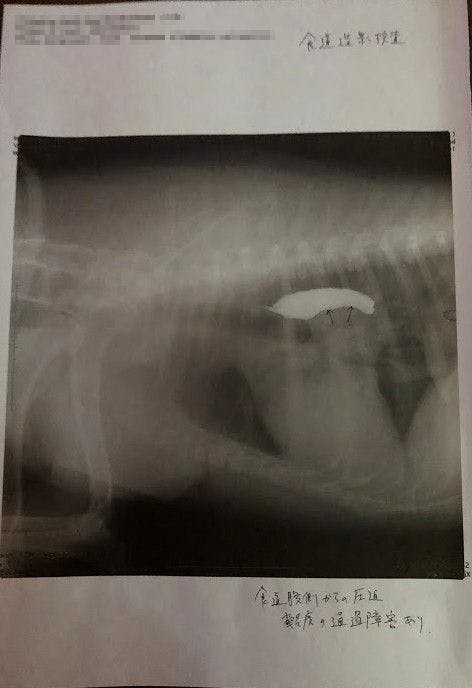

しかし段々水を吐く回数が少しずつ増えてきたのをみて、日本でも健康診断受けようと思い昨年末に動物病院で診てもらったところ、検査時で5cm程の腫瘍が体の中心(心臓近く)にあり、その腫瘍が食道を押し上げているため、飲んだ水を吐き出してしまったりしているんだろうとの事でした。

↑バリウム飲んで検査してもらった所、矢印の部分に腫瘍があり(白い部分は食道)、それが食道を押し上げているため、飲んだ水を吐いたりするとの事でした。(この時点で5センチほどの大きさの腫瘍)